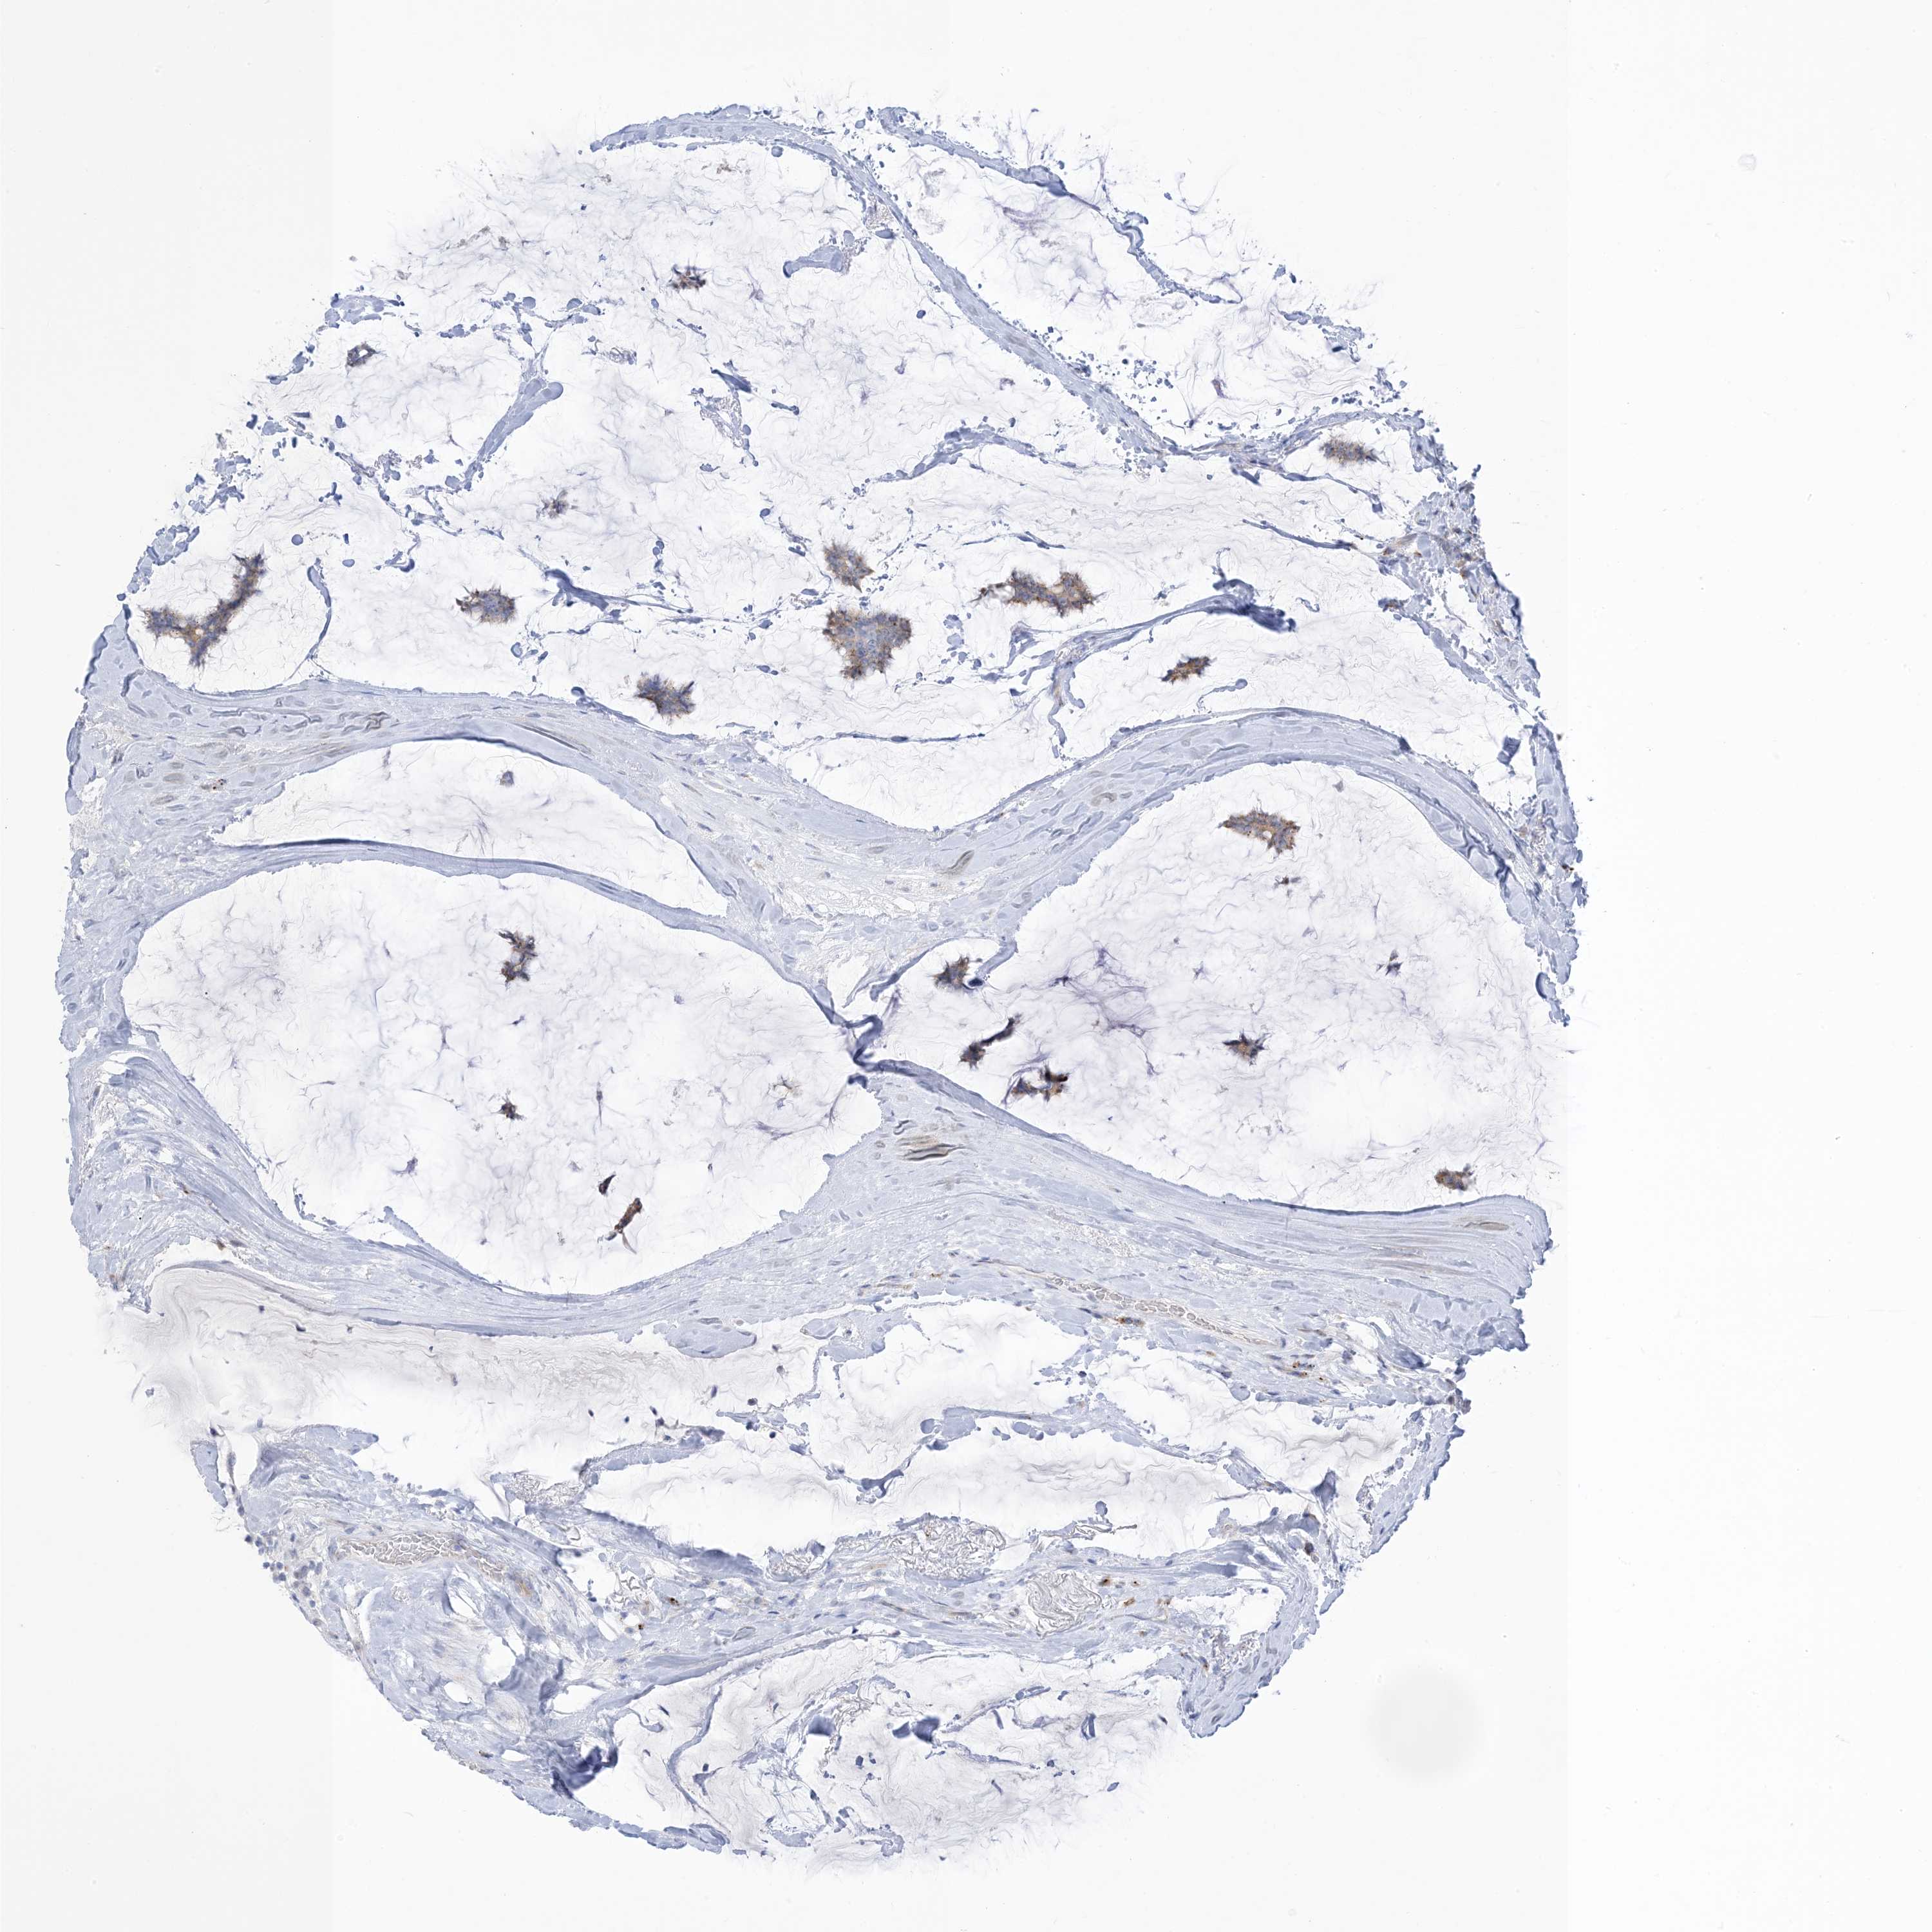

BRCA TCGA BRCA VALIDATION PROTEIN EXPRESSION